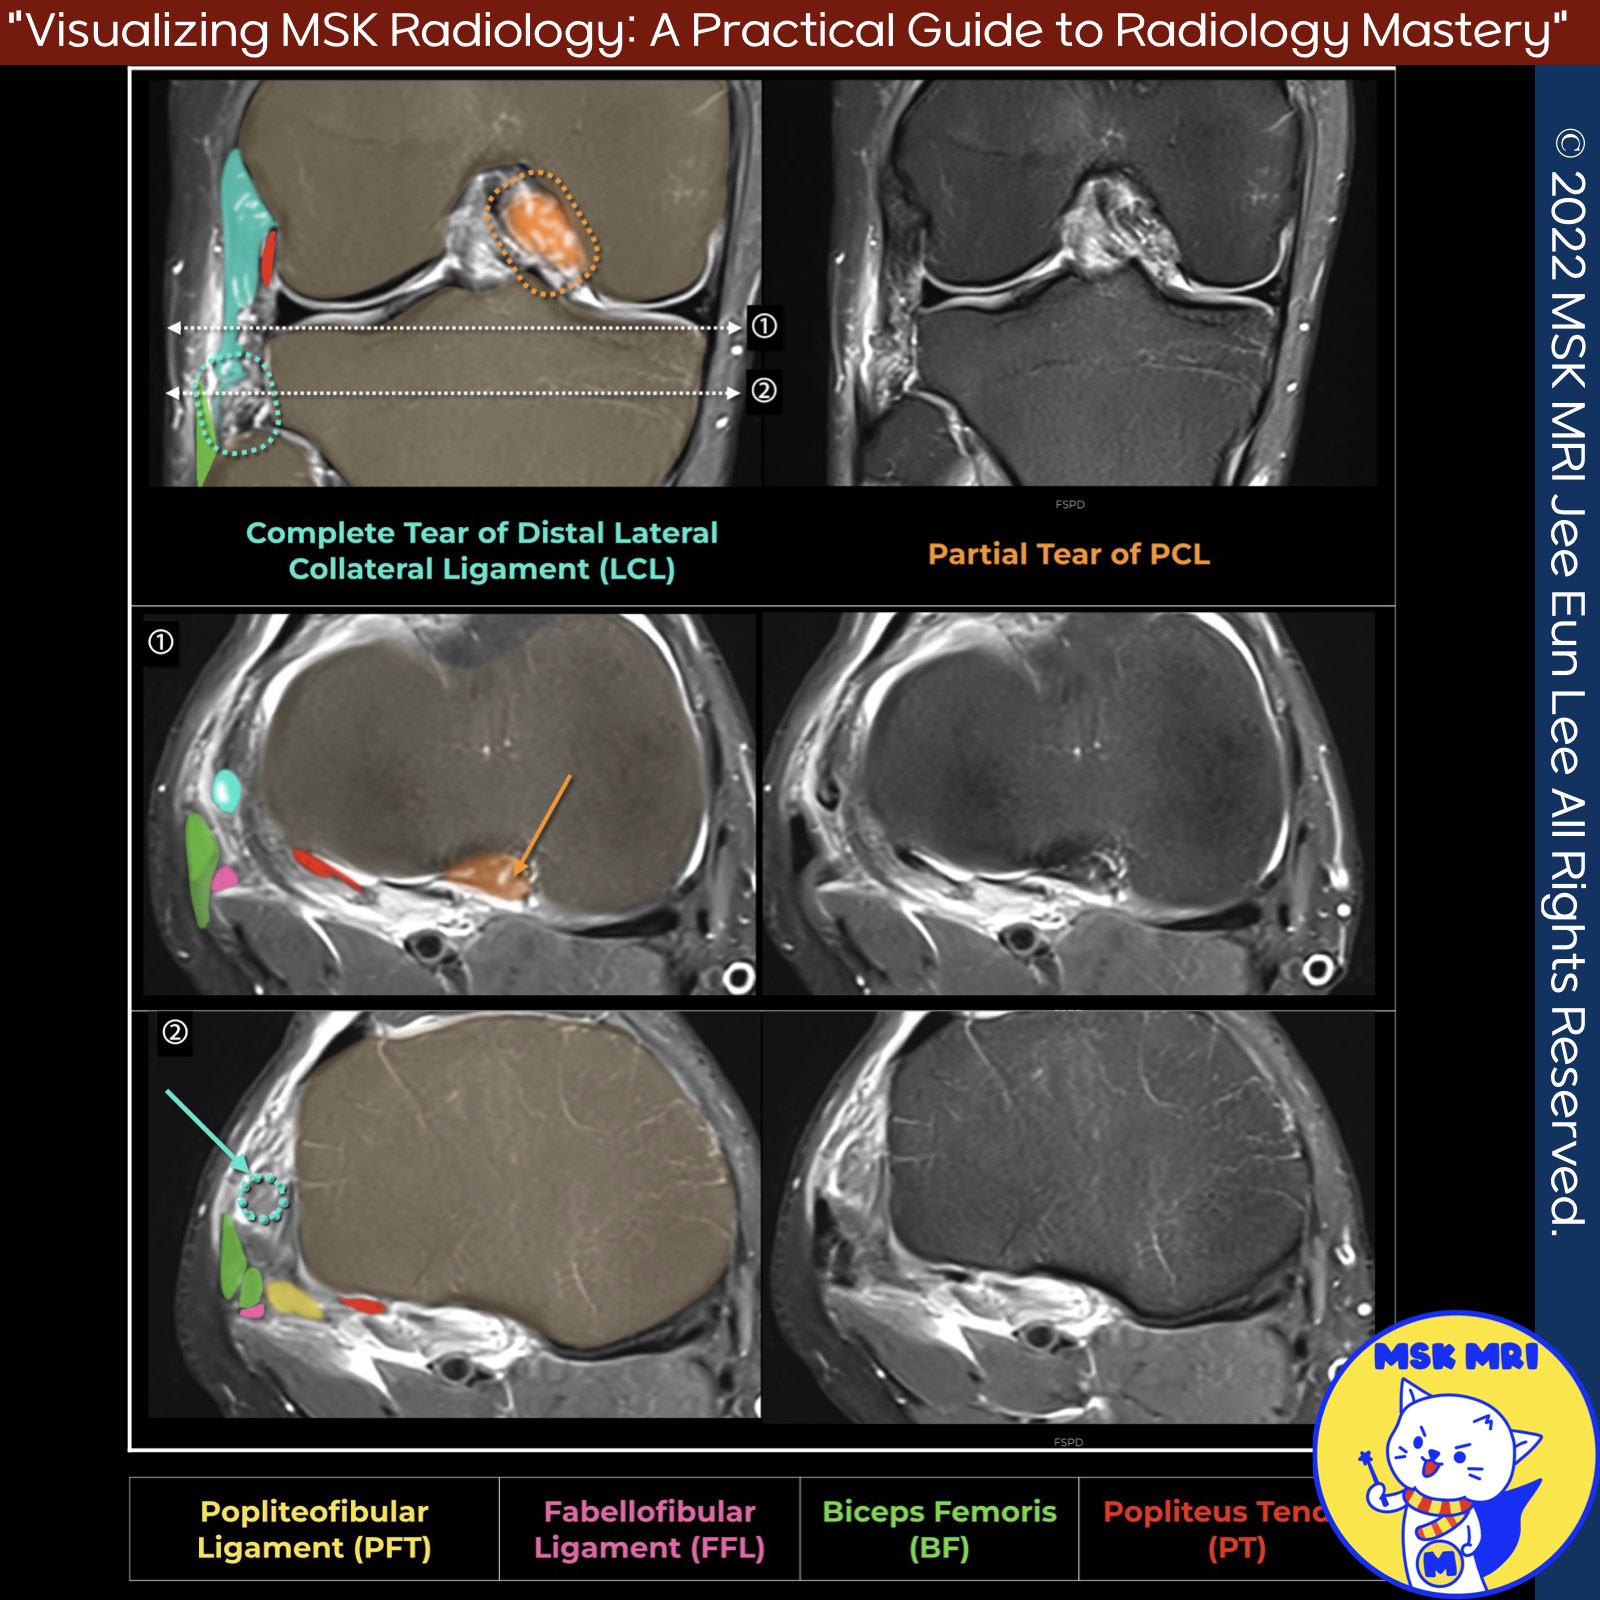

📌MRI Findings in Ligament Injuries

✅ Lateral Collateral Ligament (LCL) Injury Patterns

- Most common injury patterns of the fibular collateral ligament (LCL) include:

- According to Juhng et al., avulsion of the LCL usually occurs at its distal attachment from the head of the fibula, rather than its proximal femoral attachment.

- In complete LCL disruptions, the ligament demonstrates a wavy or serpiginous contour and loss of ligamentous continuity on MRI.

✅Associated Cruciate Ligament Injuries

- Isolated injuries to the posterolateral corner (PLC) of the knee are rare.

- PLC injuries usually occur in conjunction with injury to a cruciate ligament (ACL or PCL).